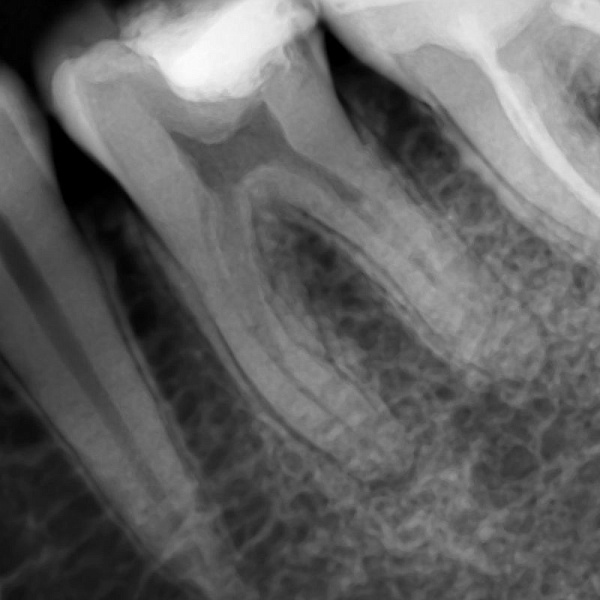

- Высококачественные снимки

- Высокая чувствительность для лучшего качества и низкая доза излучения